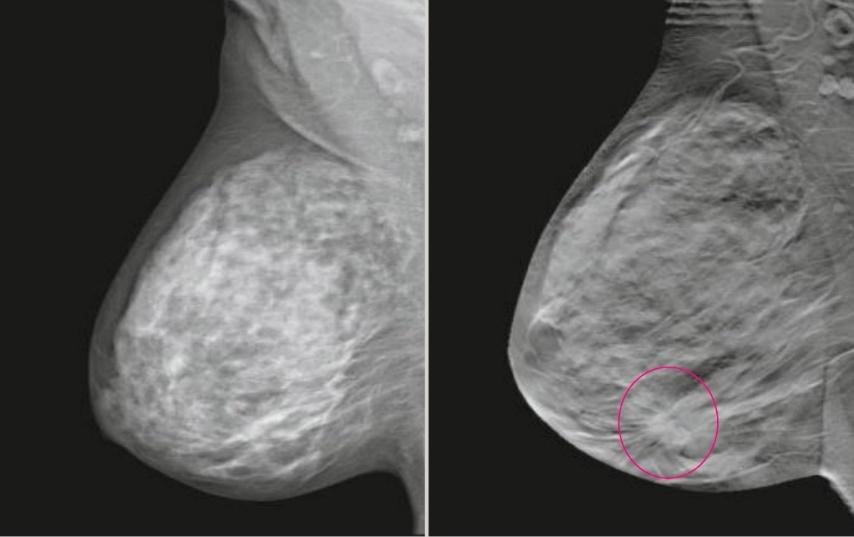

В зависимости от высоты устройства достигается коэффициент геометрического увеличения объекта исследования 1.5х, 1.8х или 2.0х.

Метод прицельной маммографии с увеличением применяется для более детального исследования определенной области молочной железы. Он отличается высокой точностью диагностики. В отличие от обычной маммографии, которая предоставляет более общую информацию о состоянии молочных желез, прицельная маммография с увеличением позволяет получить точные данные о процессах, происходящих в тканях, благодаря методу компрессии конкретного участка.